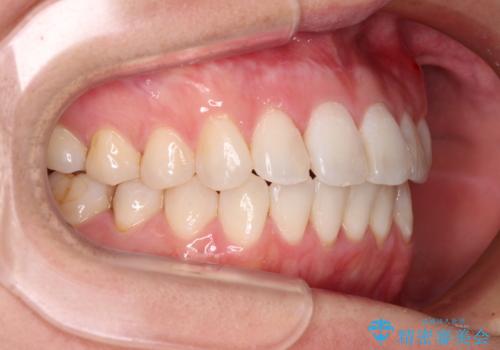

長年気にしていた前歯 インビザラインで目立たず改善

- ワイヤーではない矯正治療があると聞いたとのことで来院された患者様です。

長年前歯のデコボコを気にしていたもののワイヤー矯正に抵抗があり躊躇していたそうですが、インビザラインなら治療してみたいとのことで相談にいらっしゃいました。

インビザライン適用の歯列であったため、歯と歯の間を削るIPRを用いて改善することとしました。

下顎前歯の叢生が顕著な場合、歯列改善後に歯と歯と歯肉の間にブラックトライアングルという隙間ができてしまいます。

軽減することはできますが、完全に解決することは矯正治療のみでは不可能なため、リスクとして事前に周知しておく必要があります。